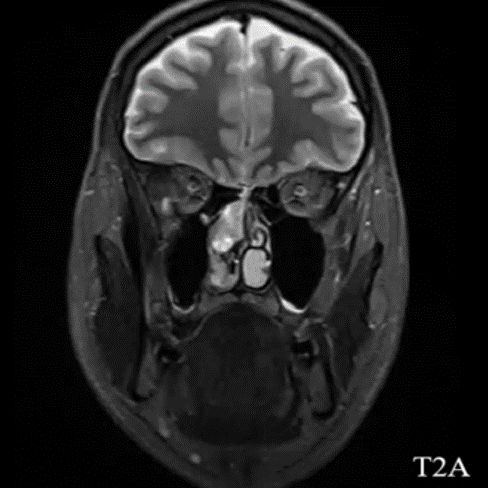

- B) Aksiyel T2A (oklar) ve T1A (oklar) görüntülerde lezyonun süperior nazal kavitede ve ara sinyal intensitede olduğu izleniyor.